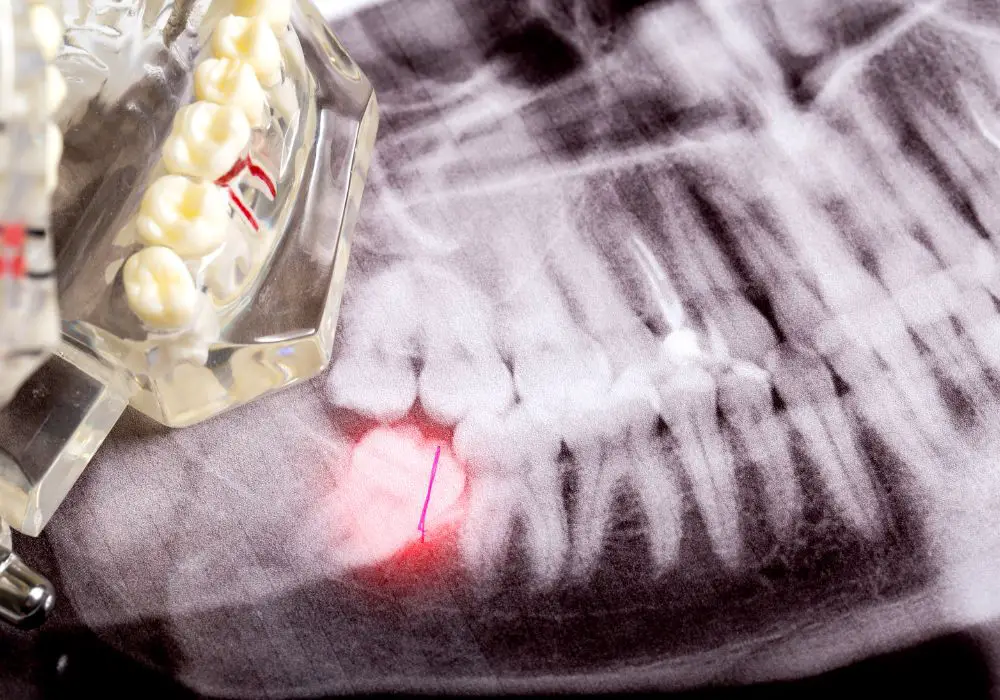

An impacted wisdom tooth is one that encounters restrictions preventing proper growth through the gum. This restriction may result in the tooth failing to erupt upright or remaining within the jaw, causing pain and other various dental complications.

Manifestation of impacted wisdom teeth can take two forms: partial emergence from the gum line, displaying only a portion of the molar crown, or complete submersion beneath the gum tissue. Despite the presentation, both scenarios share similar symptoms, contributing to diverse complications.

- Growth Angulation Abnormalities

The growth angle of wisdom teeth is a key factor in determining impaction. In an ideal scenario, wisdom teeth emerge upright behind the second molar and align perfectly with other teeth; however, challenges may arise due to limited space in a small jaw. Dentists assess the angle at which these teeth grow, identifying mesial and distal impactions, horizontal angulation, and vertical growth anomalies.

A wisdom tooth could develop toward the second molar or to the back of the mouth. These are referred to as mesial and distal impaction, respectively. It’s also possible for the tooth to be angled horizontally, applying pressure against the second molar. The vertical growth anomalies occur when the wisdom tooth seems to develop like a normal tooth but remains lodged inside the gum. If a wisdom tooth shows any of these features, it is impacted.